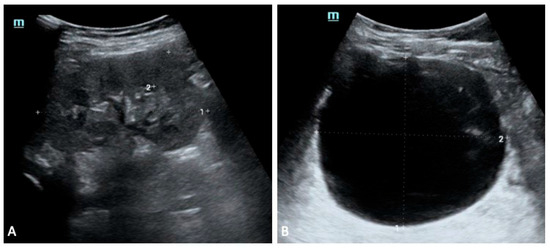

The second sibling had a milder presentation. Early scans showed bilateral multicystic involvement, with the left kidney more affected, although renal function was preserved. Mild proteinuria and phosphaturia appeared intermittently but resolved without specific intervention. By the age of five years, renal imaging had normalised, and serum creatinine and electrolytes remained within expected limits.

The youngest sibling had prenatal signs of right kidney hyperechogenicity and bilateral pyelectasia. These changes improved over time, and renal function remained stable across follow up. Occasional proteinuria and phosphaturia were noted in early life, although subsequent biochemical tests showed steadier values. Compared with the older sibling, the renal course was relatively uncomplicated, despite the early anatomical findings (Figure 3, Figure 4 and Figure 5).

Figure 4. Sibling 2. Abdominal ultrasound exam performed at 5 years of age; images exploring the right (A) and left (B) perirenal spaces of the abdominal cavity. (A) shows a normal-sized kidney [pole-to-pole diameter approximately 79 mm (dotted line 1), anterior parenchymal thickness of 17 mm (dotted line 2)], with normal echogenicity. On the other hand, the left kidney structure is diffusely altered with several cysts seen within, ranging in size from a few millimeters to some centimeters (the most prominent one approximately measures 81 mm × 91 mm in the sagittal plane (dotted lines 1 and 2 in (B)).